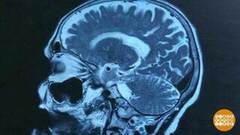

Про людей с болезнью Альцгеймера говорят, что они впали в детство. Они все забывают, не узнают близких. Некоторые уже не могут себя обслуживать. У больных изменяется структура мозга, нарушается проводимость нервных импульсов, клетки мозга начинают гибнуть.